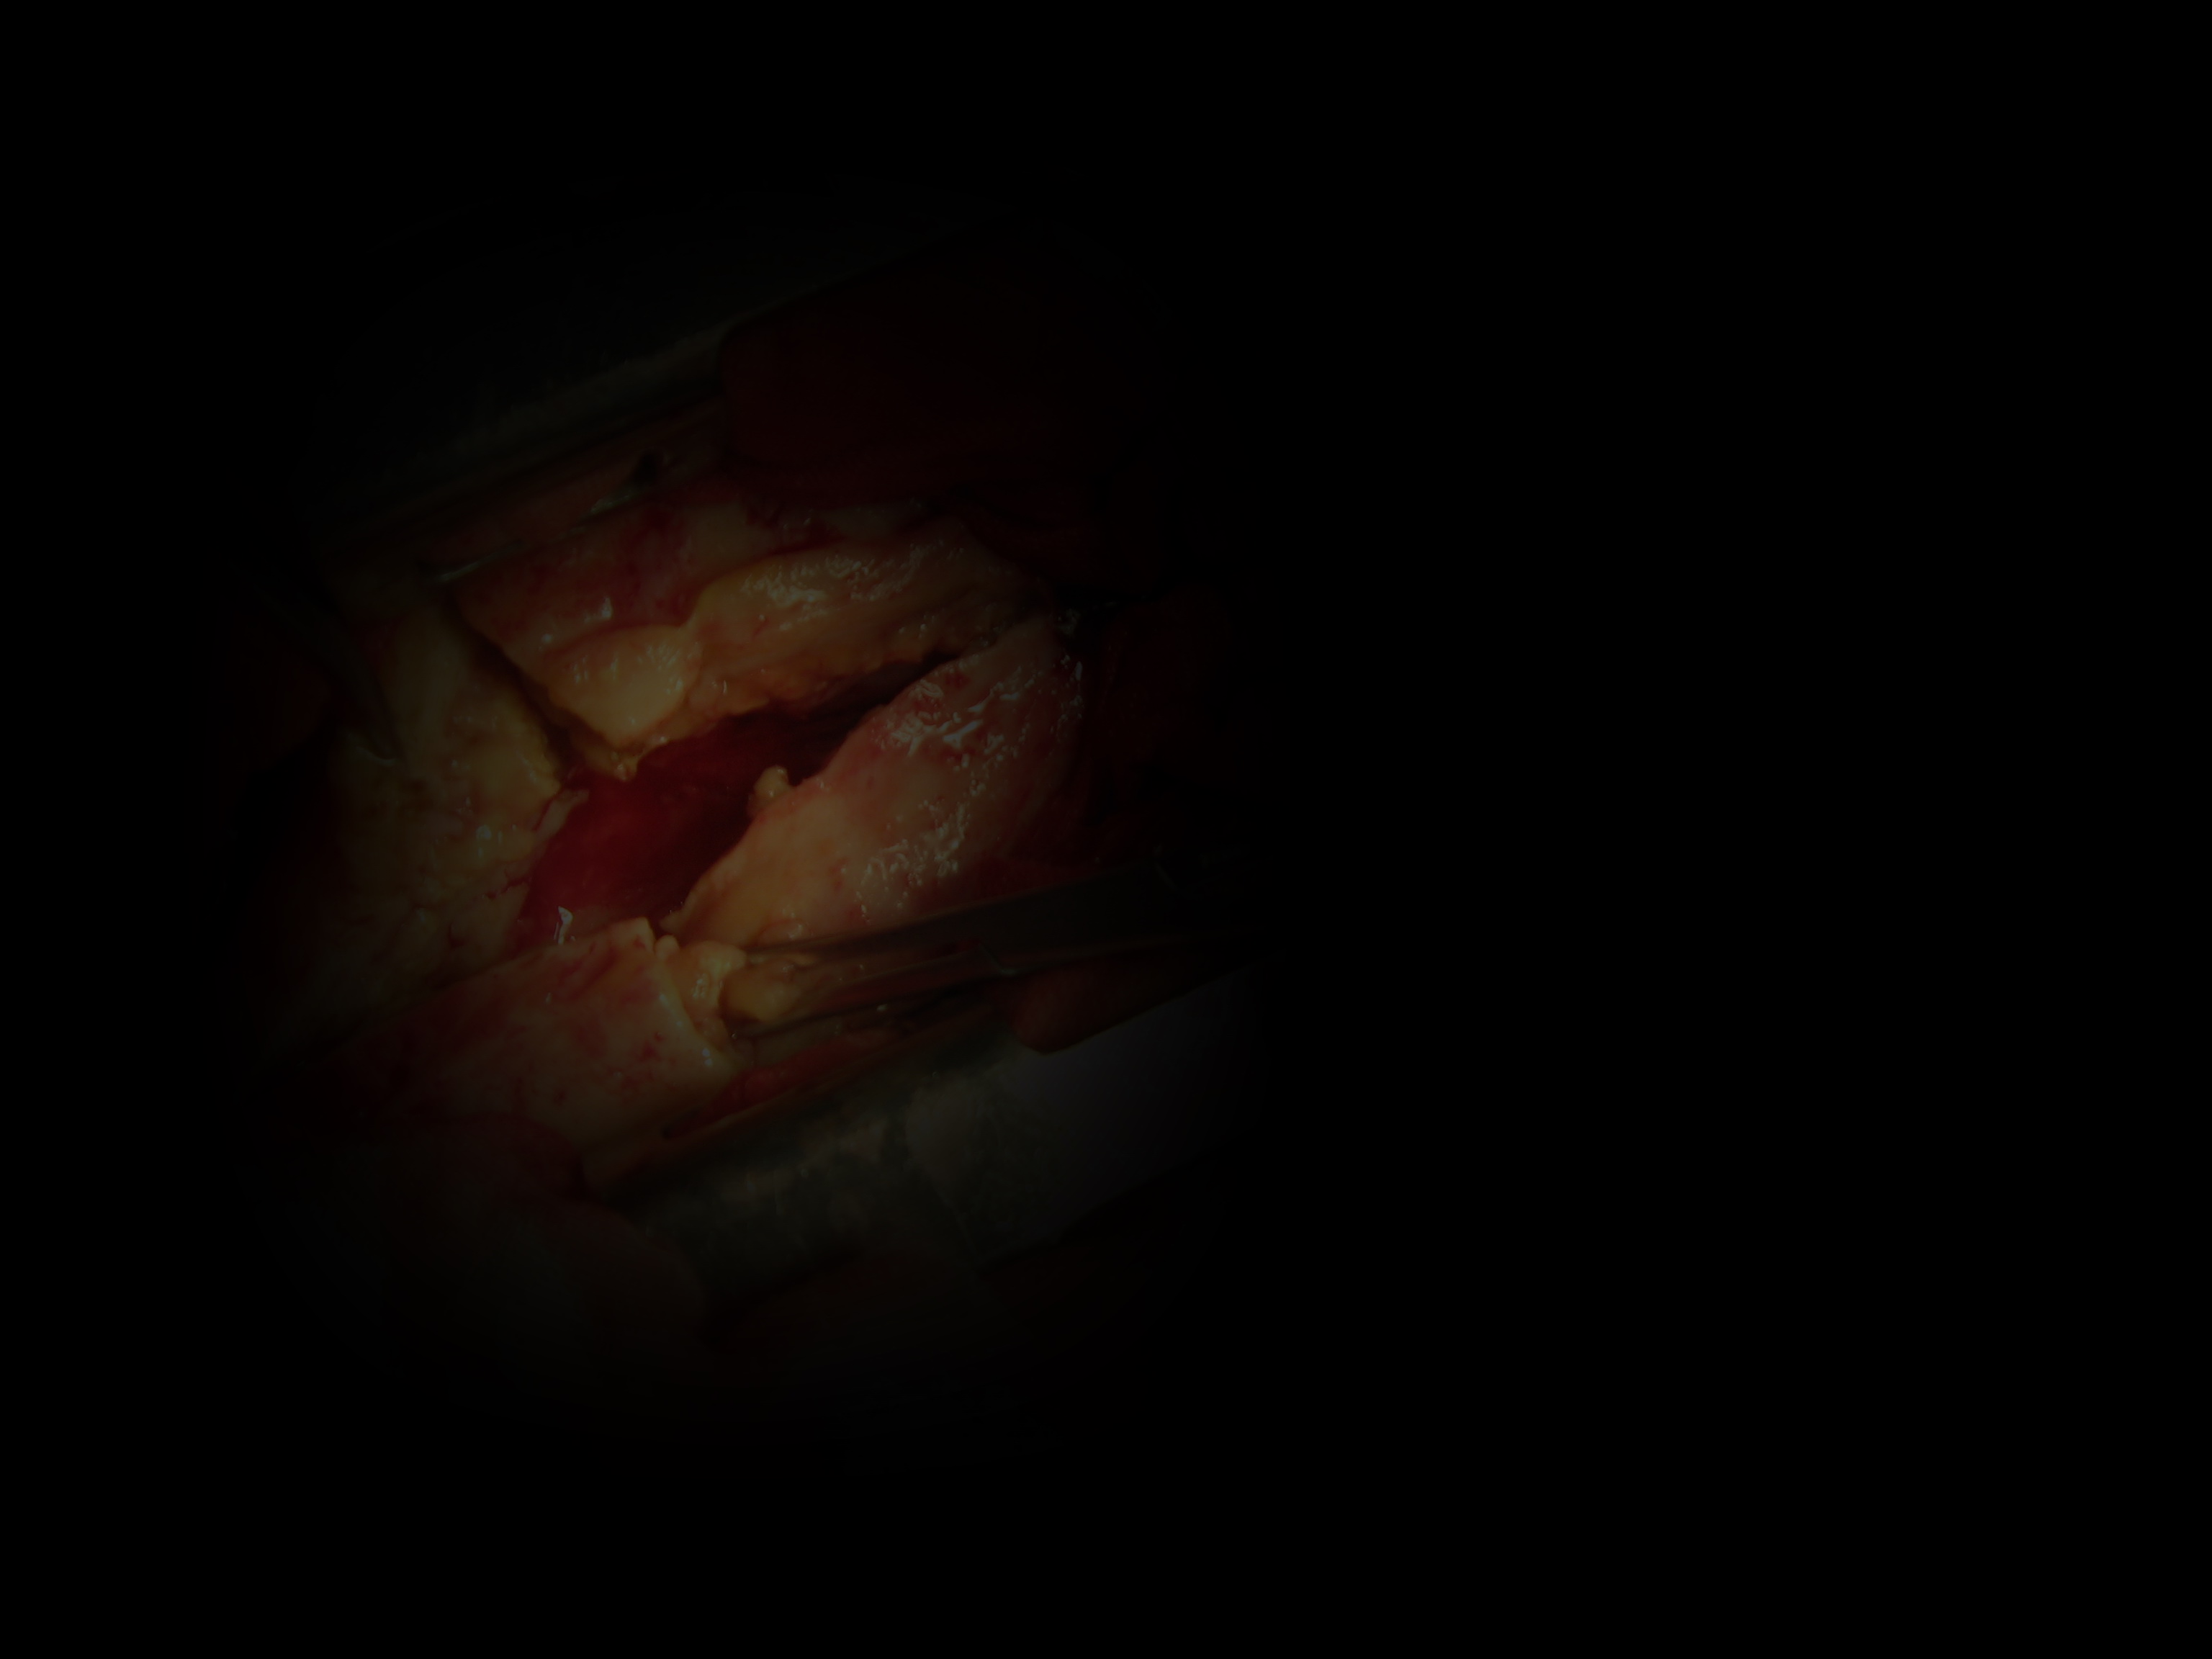

术中见胸膜增厚约2cm ,包裹性脓胸